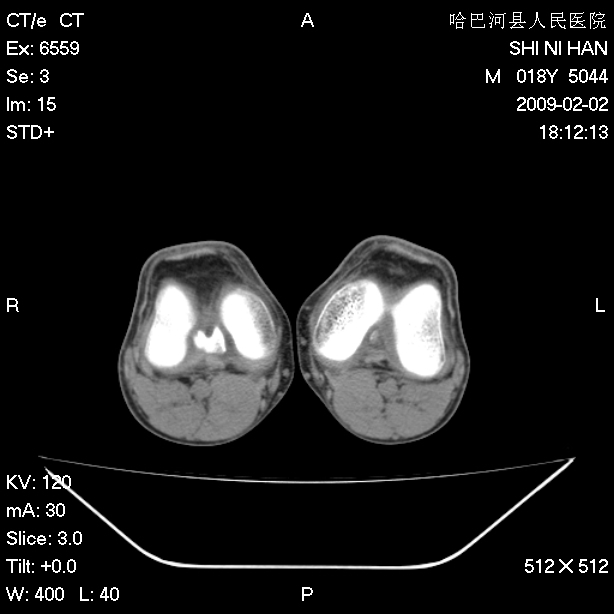

标题: CT17889:外伤后右膝关节反复疼痛3年余 [打印本页]

标题: CT17889:外伤后右膝关节反复疼痛3年余

ct未见明显异常。关节腔未见明显积液,半月板未见明显撕裂。但最好还是mri看看韧带及半月板情况。